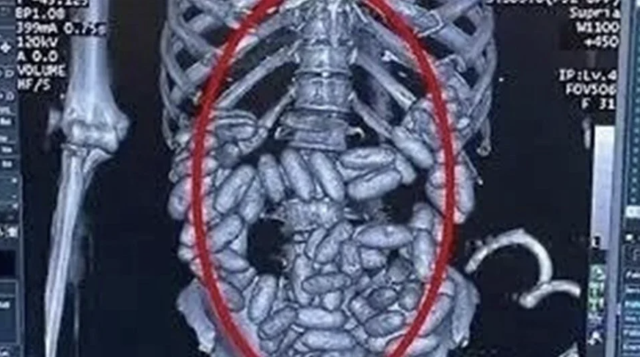

Sabah gazetesinin haberine göre, Kolombiya'da uyuşturucu ticaretine devam eden ve kısa sürede Güney Amerika'dan Avrupa'ya kokain ticareti yapan uluslararası bir suç örgütünün lideri durumuna gelen Müldür, "yutucu kurye" yöntemiyle uyuşturucuları kuryelerin midelerinde göndermeye başladı.

Müldür'ün kuryelerinden Nijerya asıllı 22 yaşında bir kadın Sao Paulo'dan havayolu ile İstanbul'a geldiğinde midesinde 1 kilogram ağırlığında olan 82 kapsülle yakalandı.